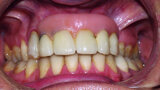

Fig. 38: Final cosmetic check-up showing correct lip support with the new extremely reduced false gingiva.

Fig. 39: Final cosmetic check-up showing correct lip support with the new extremely reduced false gingiva.